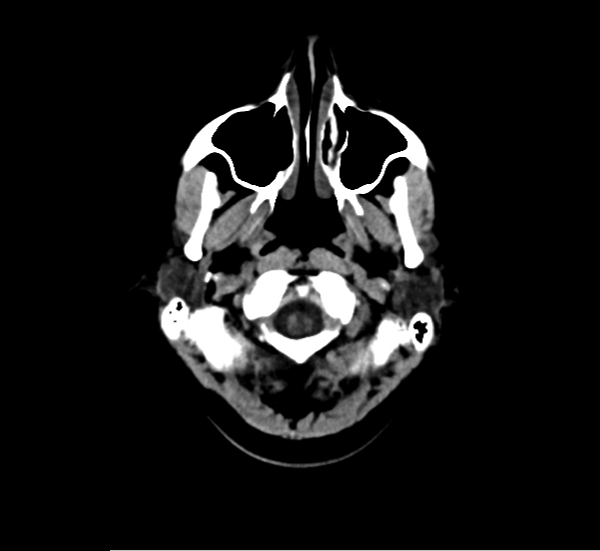

CT Brain Anatomy